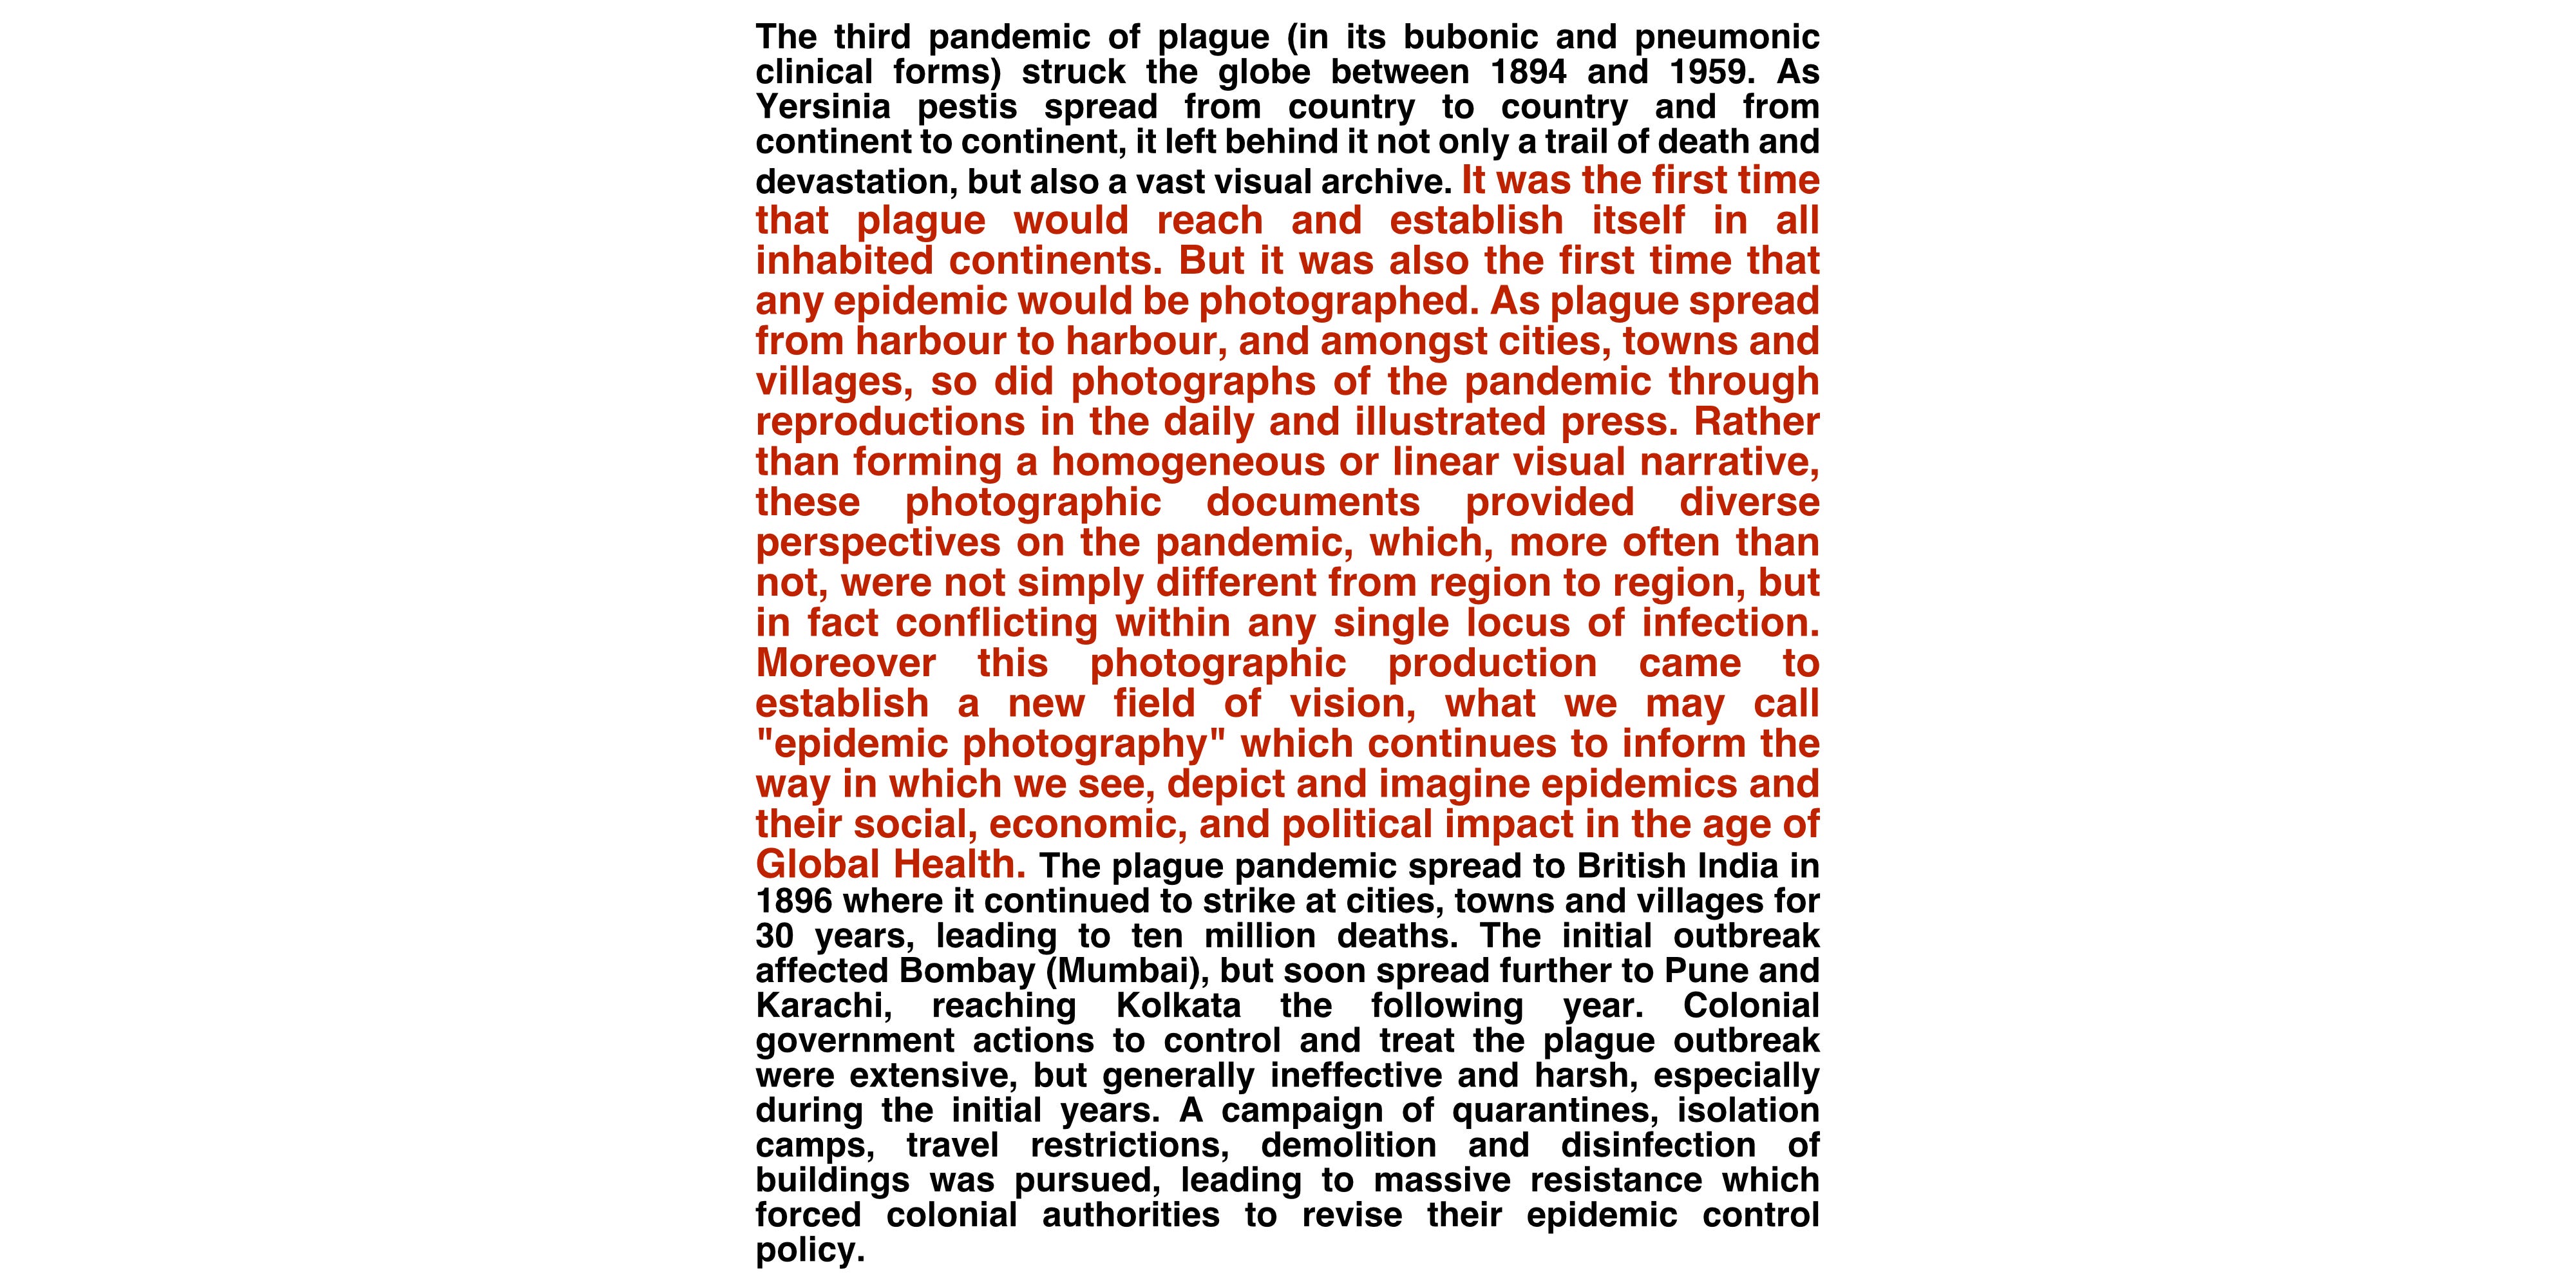

Last Friday we were fortunate to have with us once more as a panelist, from Tripoli, Nada Harib, for whom COVID-19 is just another layer of concern atop the war in the Libyan capital.

We highlight her work here and draw attention to the courage that she and many others in her situation have to find inside themselves in order to live through and document these trying times.

We begin this week’s edit with an extract from Nada Harib’s recent whatsapp message to Daniel Schwartz regarding her possible participation in a workshop programme.

(Lines of text have been enlarged for the purpose of sharing her message here on this ASV platform. Her original message was in plain, single point font.)

There’s no shortage of players in Libya’s conflict. But few champions for peace. <The Conversation 25 May 2020>

2/ Some Libyans don’t recognise the danger of the pandemic even after the discovery of the first confirmed case of COVID- 19 in the country. Some don't take it seriously and treat it as a joke; some are too busy with other challenges like water and electricity cuts, and gas and bank queues. Some are busy because they’ve been displaced from their homes because of the war’s escalation. And some are in mourning because of the loss of their loved ones caused by indiscriminate shelling. There are some who are informed and rightly concerned because of the virus and are doing their best to raise awareness in this ever-changing situation.

My mom and I went to the supermarket and wore our masks and gloves for the first time. Such a strange feeling to one of just a few wearing them— many eyes staring at us. There weren’t too many people in the supermarket. The shelves of food haven’t emptied yet. We bought extra food to store before the crowds begin. Now, after a couple of weeks of quarantine, there are 9 people who have tested positive for COVID-19.

The government has announced a 24-hour curfew for 10 days that is going to start on the 17 of April to reduce the spread of the virus.

The streets are crowded and packed with cars and the supermarkets have long queues too. The holy month of Ramadan is getting closer and more people are realising the danger of the pandemic.

Here is a photo of a young man waiting for people to sanitise their hands before entering the supermarket. March 22nd, 2020. Tripoli, Libya. © Nada Harib